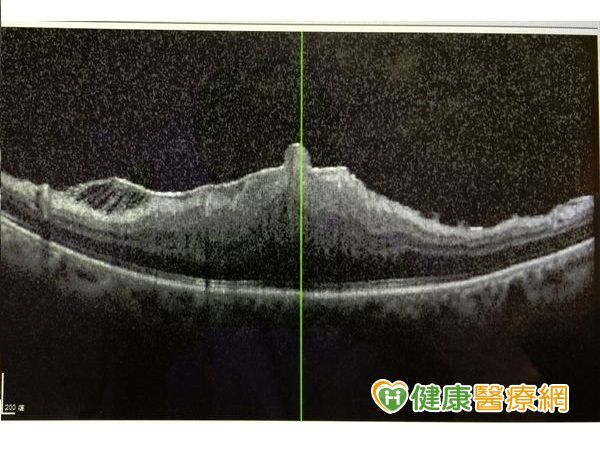

▼OCT切面可見其高高隆起,通常皺褶撕除後仍改善不多。

收治這名婦人的新竹馬偕醫院眼科主治醫師張聰麒表示,經由光學斷層掃描後發現,該名婦人的黃斑部皺摺相當堅厚,主要是因為眼球內部曾發炎導致,皺摺的位置就位於眼球正後方,黃斑部因為皺折拉扯成一團,視力僅有0.1,且不僅影響視力,更會造成視覺扭曲模糊。